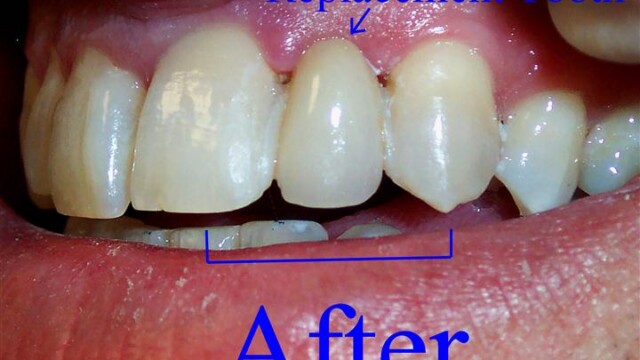

Restorative Dentistry

Restorative dentistry services focus on repairing teeth damaged to cavities, tooth decay, or trauma. From our beginning, it has been our goal to help our patients restore strength and structure to their smiles. We are committed to helping your smile stay beautiful and healthy for a lifetime. We incorporate the latest dental technology to ensure you receive the most advanced care. Our restorative services include:

Crowns